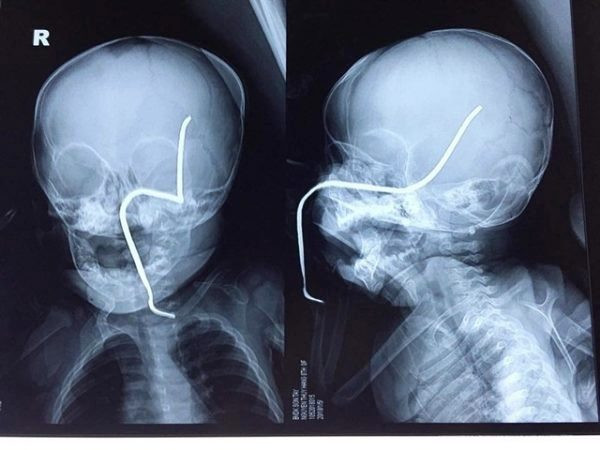

Hình ảnh phim X-quang của cháu H. cho thấy thanh sắt đâm vào gò má trái, xuyên lên vùng não thái dương.

Theo ThS.BS Hồ Trung Luân, khoa Ngoại Thần kinh - người trực tiếp phẫu thuật cho bệnh nhi, ca mổ khá khó khăn do thanh sắt đâm vào gò má trái qua tổ chức phần mềm của má, đâm thủng sàn sọ, xuyên qua vùng não thái dương và vùng đỉnh sát các mạch máu lớn.

“Thanh sắt cũ, giòn nên rất dễ gãy, lại nằm sát các mạch máu nên nguy cơ chảy máu trong mổ là rất lớn, đồng thời nguy cơ nhiễm trùng não, áp-xe não cũng rất cao” – BS. Luân cho hay.